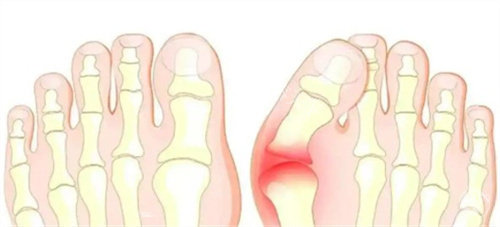

困扰多年的双脚难题

我的双脚大脚趾根部长期以来一直向外突出,形成难看的骨凸。不仅穿鞋经常磨脚,走路时间稍长就会隐隐作痛。每到夏天,我总是避免穿凉鞋,担心别人看到我变形脚型的异样眼光。这种困扰像块沉甸甸的石头压在我的心头,让我渴望找到解决之道。

接诊的医生经验充足且态度和蔼。他仔细检查了我的双脚,让我做了一些简单动作来观察脚部活动情况,还结合X光片详细解释了拇外翻的形成原因和发展程度。这种正规的讲解让我对自己的病情有了清晰认识,也对后续治疗增添了信心。